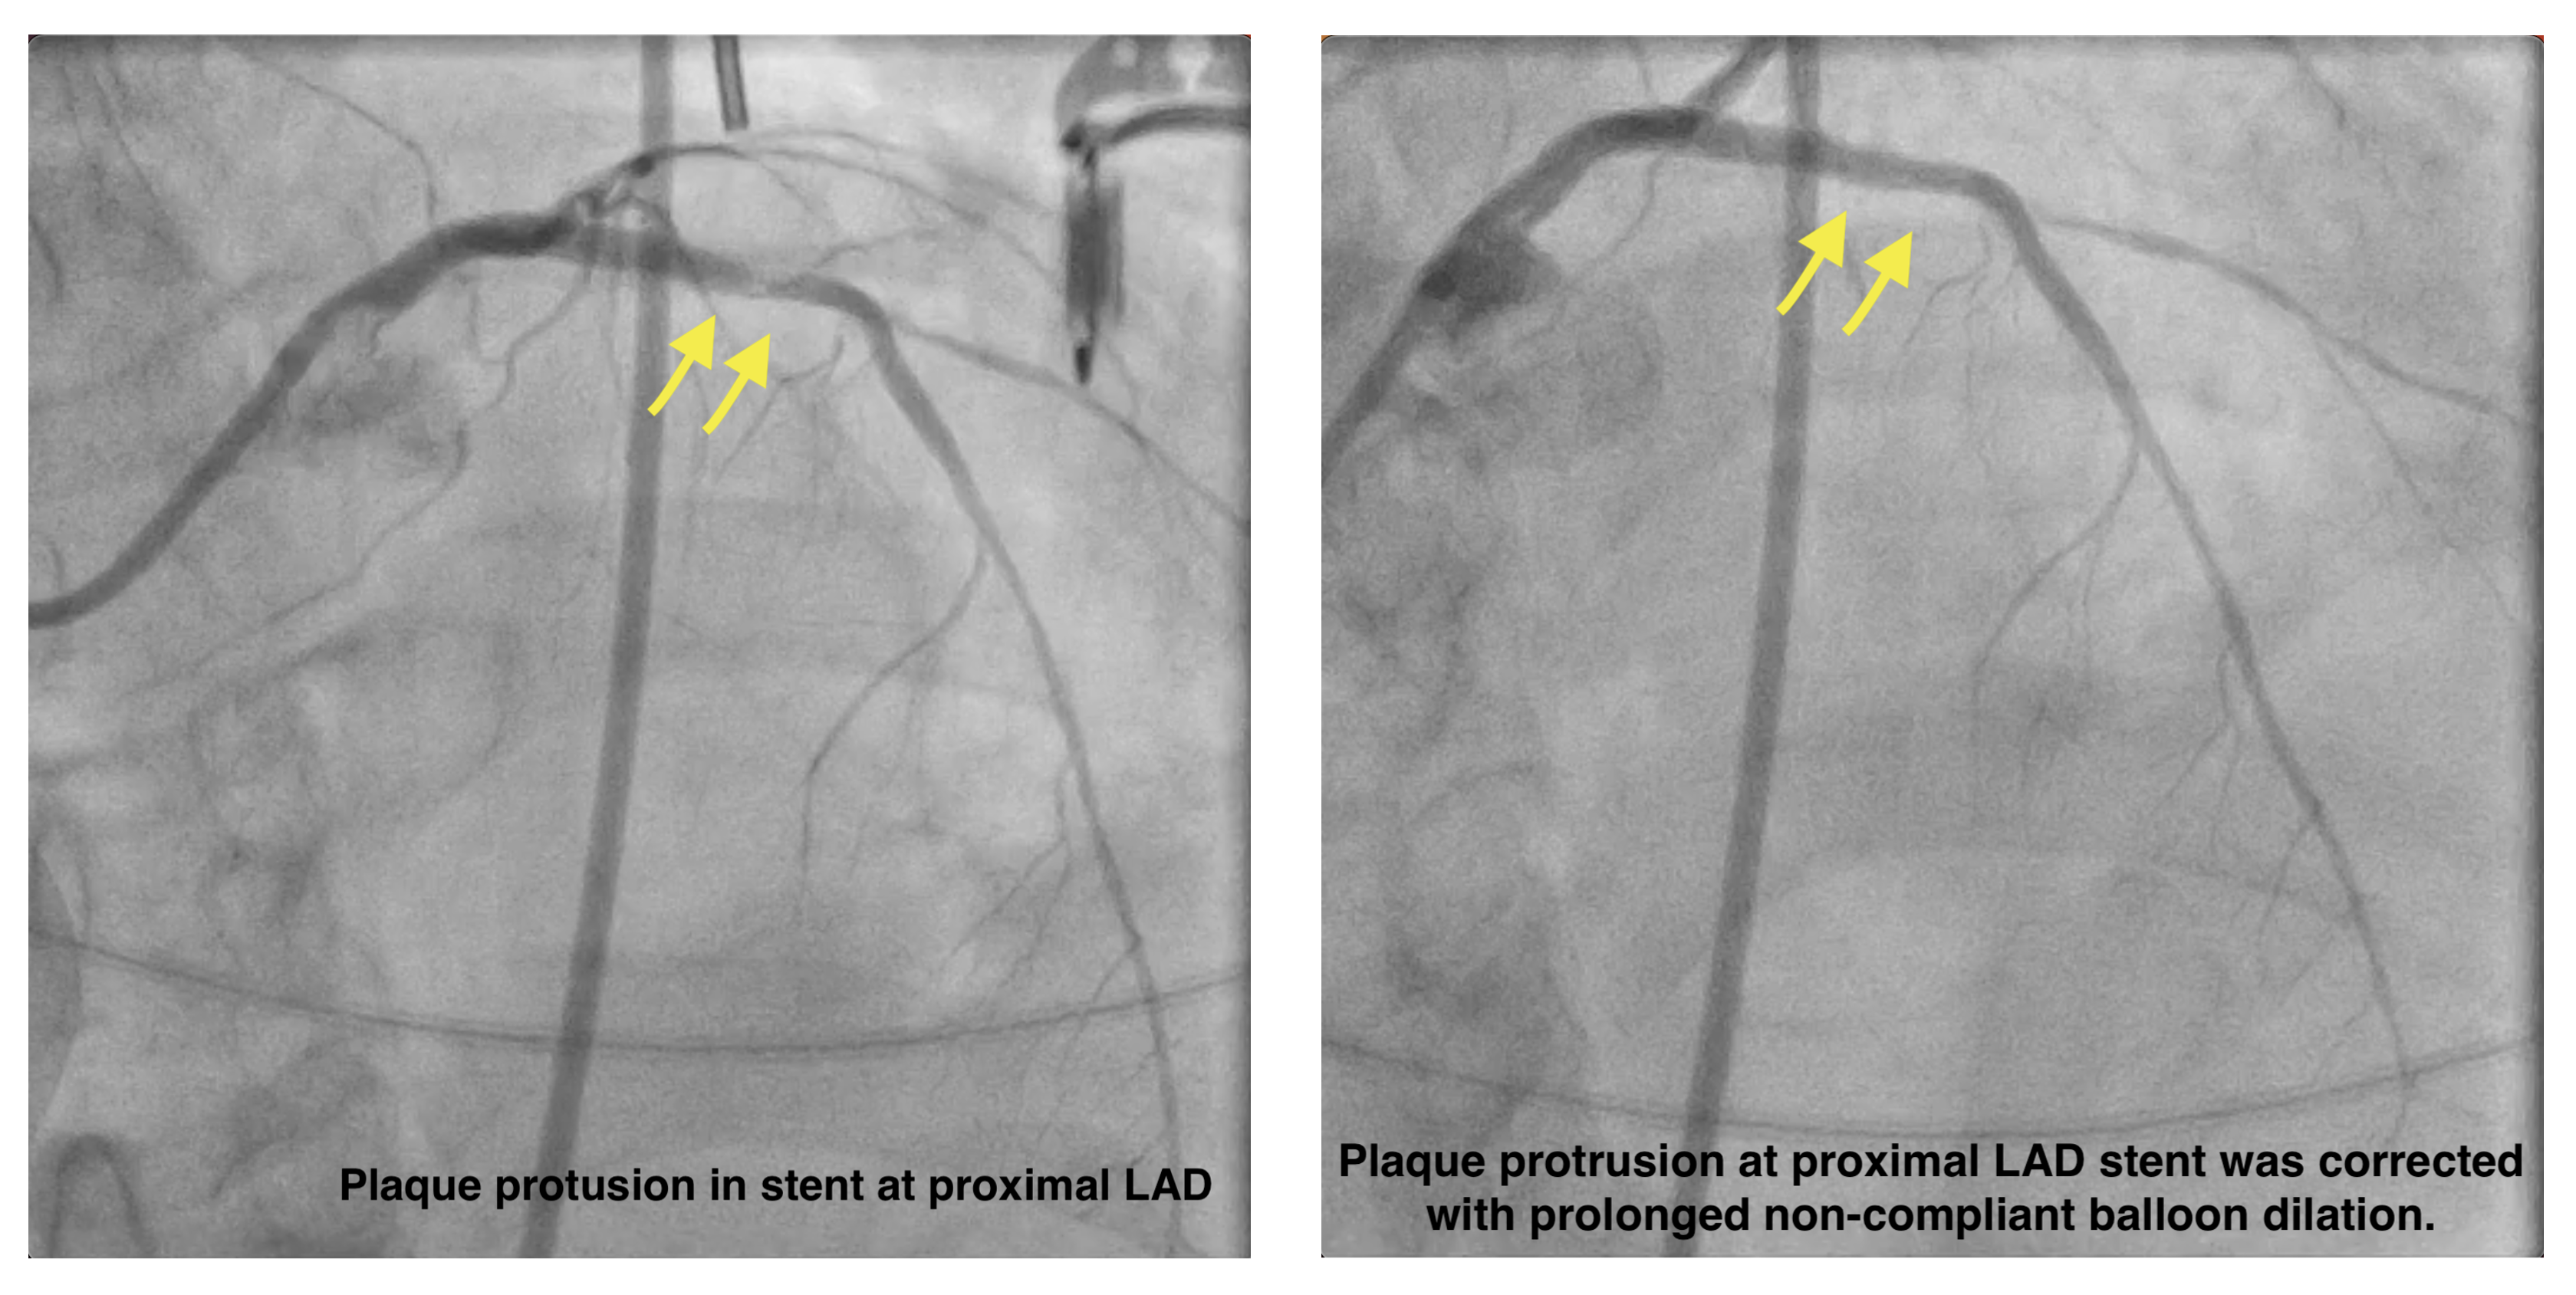

Access site: RRA 6F sheath, EBU 3.5 6F guiding catheter. IABP was inserted via RFA for hemodynamic support. A BMW guidewire (GW) was advanced into the LAD, & thrombus was aspirated. A Sion GW was then placed in LCX. IVUS guided a provisional strategy from LM to LAD restoring flow quickly. The lesion was pre-dilated with a 2.0 ¡¿ 20 mm balloon & a 2.5 ¡¿ 10 mm scoring balloon. Biomatrix Alpha stents (3.5 ¡¿ 36 mm & 2.5 ¡¿ 24 mm) were deployed from the LM to mid LAD & post-dilated. The LCX became jailed, so the T-and-Protrusion technique was initiated as a bailout, & a Biomatrix Alpha 2.5 ¡¿ 19 mm stent was positioned for TAP. After TAP, acute thrombosis developed at the neocarina of the LM. The patient received adequate heparin, intracoronary eptifibatide, & vasopressors. The procedure was stopped after achieving TIMI 3 flow in LAD & resolution of ST elevation. The patient was transferred to the ICU for intensive antithrombotic therapy. 3 days later, a relook angiogram via the LFA (EBU 3.5 7F) showed total LCX occlusion. IVUS confirmed excessive LCX stent protrusion into LM. Reverse Double Kissing Crush was performed. The protruded LCX stent was crushed with a 4.0 ¡¿ 12 mm non-compliant balloon, Sion Blue GW was advanced through the proximal strut, & final kissing inflation with proximal optimization was completed. Plaque protrusion at proximal LAD stent was corrected with prolonged NC balloon dilation. Final IVUS & angiography showed good result.